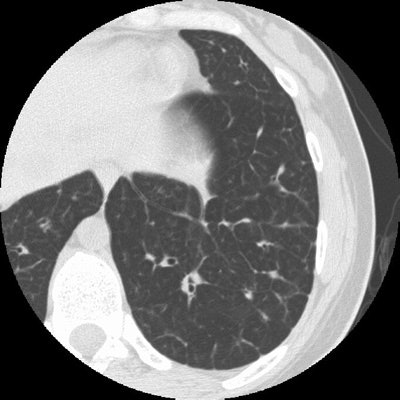

Sarcoid Stage 4:

The case below in from a patient with a history of sarcoid. The HRCT examination demonstrates interstitial lung disease with peripheral traction bronchiectasis that has been stable over the past several years. (Click image to enlarge)